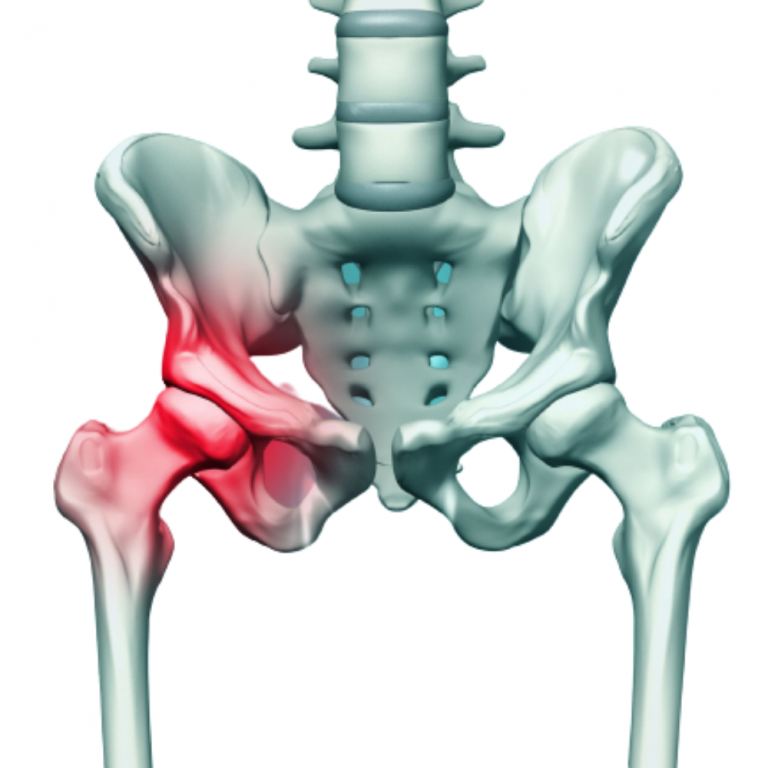

Dr. Tripathi specializes in the intricate field of pelvic and acetabular surgery, a branch of orthopedics dealing with complex fractures and injuries of the pelvic girdle and hip socket. His extensive training and experience enable him to handle the most challenging cases with precision and care. He is adept at both surgical and non-surgical management of these conditions, ensuring comprehensive care tailored to each patient’s needs.